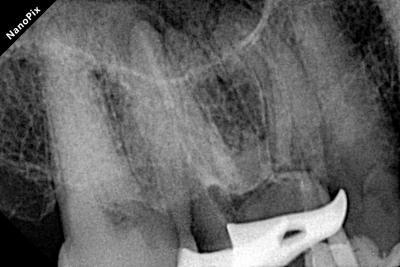

Shaping with Perfection: The canals were shaped using the DENCO Only One File Blue (up to 40.06). The file navigated the extreme curvatures and calcifications flawlessly without any transportation.

Showcasing perfectly tapered and centered canal preparations.

Verifying the precise tug-back fit of the gutta-percha cones.

Radiograph of mesio buccal root canals during obturation